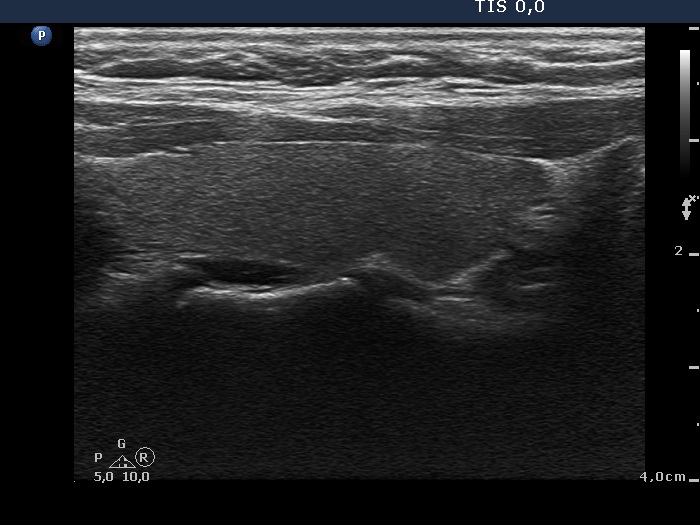

The operated thyroid - case 632

Three years after surgery (ultrasonographic picture 4)

Left lobe, longitudinal scan.